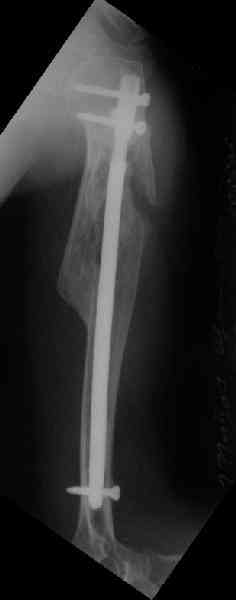

Здесь нет необходимости в серкляже. Вмешиваться на промежуточных отломках приходится, если есть угроза перфорации кожи, или промежуточный отломок попал в фасцию, как пуговица в петлю. В приложении сегментарный оскольчатый перелом плеча в проксимальном отделе, фиксированный больщеберцовым стержнем. Как видите, обошлось без серкляжа. Функция полная.

Это укороченный большеберцовый стержень, которые делает предприятие "ЦИТО".

Доступные на тот момент гвозди для плеча имели худшие возможности фиксации в коротком проксимальном отломке.